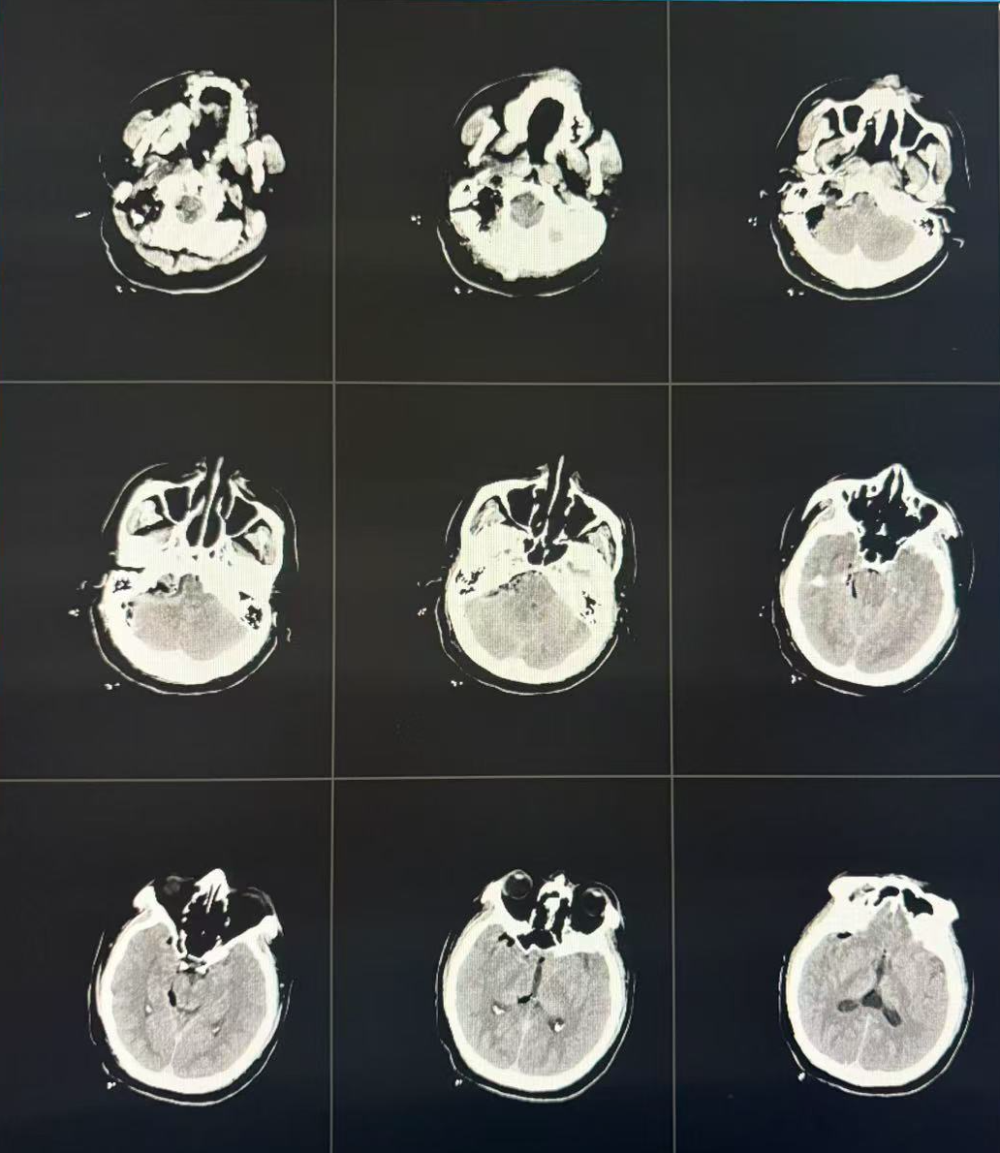

术后CT检查

术后病理结果显示为神经鞘瘤。经过两周精心治疗与护理,患者生命体征平稳,面瘫、声嘶、饮水呛咳等问题均得到显著改善,并康复出院。此次手术的成功,充分展现了交大一附院榆林医院在复杂颅底肿瘤诊疗领域的技术突破,为陕甘宁蒙晋交界区群众提供了更优质的医疗保障。